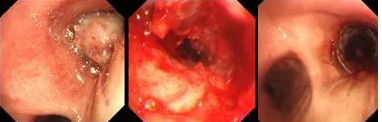

原來,秦爺爺入院時(shí)診斷為“右主支氣管”鱗狀細(xì)胞癌伴壞死。他的右主支氣管被腫瘤完全堵塞,混合性狹窄。面罩吸氧10升/分的狀況下,指脈氧只有85%,無法平躺,呼吸困難,病情十分危急,隨時(shí)有生命危險(xiǎn)。

經(jīng)評(píng)估并與家屬溝通同意后,歐陽海峰副院長(zhǎng)決定為患者實(shí)施TTS氣道支架手術(shù)。手術(shù)當(dāng)天,在麻醉手術(shù)中心的配合下,歐陽海峰副院長(zhǎng)為患者在局麻下快速凍切腫瘤組織,實(shí)現(xiàn)右主支氣管再通,并經(jīng)氣管鏡活檢孔道迅速植入14*30 TTS支架一枚。支架植入過程耗時(shí)僅6秒,迅速緩解了患者的氣短瀕死癥狀。